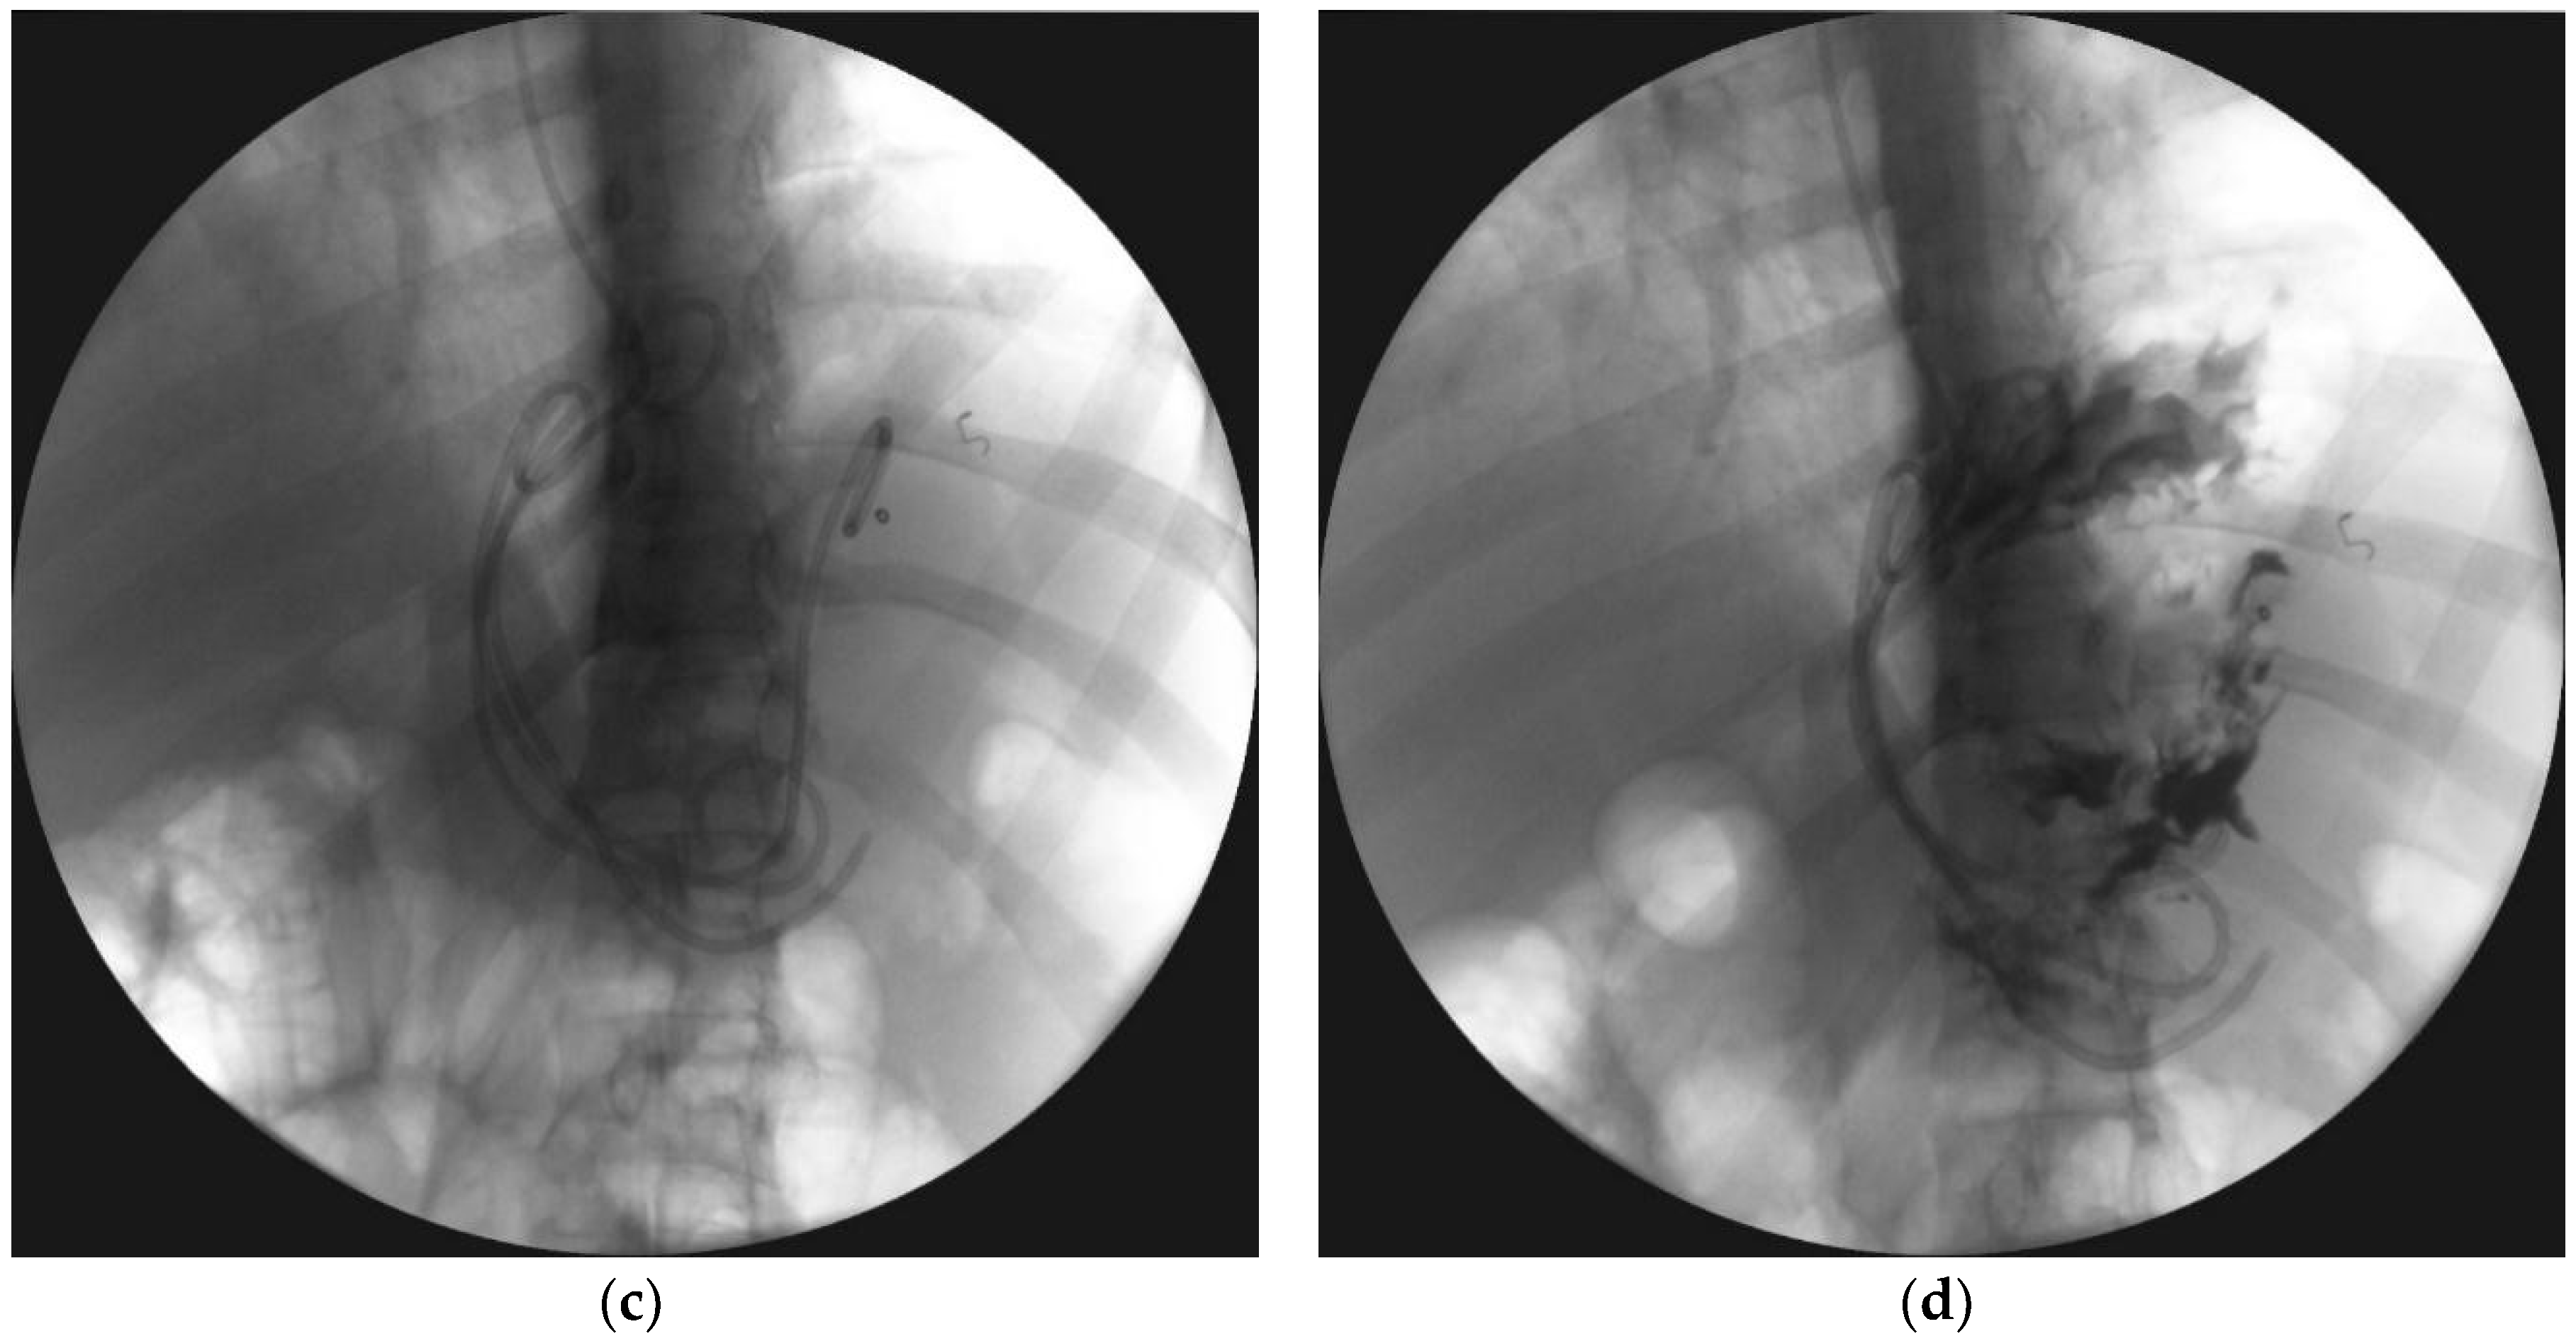

4. Transpapillary Endoscopic Drainage

- Smoczyński, M.; Jagielski, M.; Jabłońska, A.; Adrych, K. Endoscopic necrosectomy under fluoroscopic guidance- a single center experience. Wideochir. Inne. Tech. Maloinwazyjne. 2015, 10, 237–243. [Google Scholar] [CrossRef] [PubMed]

- Smoczyński, M.; Jagielski, M.; Siepsiak, M.; Adrych, K. Endoscopic necrosectomy through the major duodenal papilla under fluoroscopy imaging. Arch. Med. Sci. 2018, 14, 470–474. [Google Scholar] [CrossRef] [PubMed]